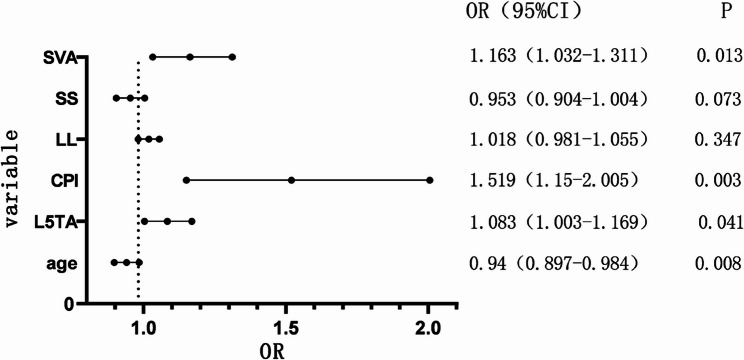

Multivariate binary logistic regression analysis was conducted on the statistically significant variables (collinearity diagnostics confirmed all variance inflation factors were < 5), revealing that Age, L5TA, CPI, and SVA are factors influencing preoperative CIB (p < 0.05) (refer to Table 5, and forest plot demonstrated in Fig. 6). ROC curve analysis revealed the following AUC (Area Under the Curve) values: age (AUC = 0.40), L5TA (AUC = 0.69), SVA (AUC = 0.68), and CPI (AUC = 0.67). The results shown in Fig. 7 indicate that age is a protective factor for CIB. Patients with DS who are under the age of 60.5 are less likely to experience CIB. Additionally, L5TA > 5.75°, CPI > 3.55°, and SVA > 5.305 cm are risk factors for the occurrence of CIB in patients with DS.

Table 5: Multivariate binary logistic regression analysis

| B | Standard error | Wald χ2 | OR | p | |

|---|---|---|---|---|---|

| Age | −0.062 | 0.024 | 7.005 | 0.94 | 0.008 |

| L5TA(°) | 0.08 | 0.039 | 4.172 | 1.083 | 0.041 |

| CPI(°) | 0.418 | 0.142 | 8.673 | 1.519 | 0.003 |

| SS(°) | −0.048 | 0.027 | 3.224 | 0.953 | 0.073 |

| LL(°) | 0.017 | 0.019 | 0.883 | 1.018 | 0.347 |

| SVA(cm) | 0.151 | 0.061 | 6.114 | 1.163 | 0.013 |

Abbreviations: L5TA L5 Tilt Angle, CPI Coronal Pelvic Inclination, LL Lumbar Lordosis, SS Sacral Slope, SVA Sagittal Vertical Axis